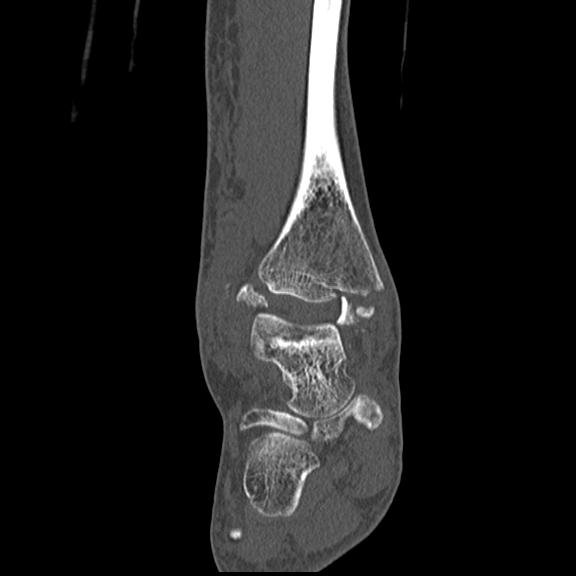

102755 1/4 2R 1/15 2R 右足関節 68歳女性 右三果脱臼骨折